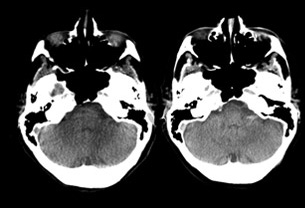

Der Arbeitsablauf der Direct to Angio Suite bietet wertvolle und zeitsparende Unterstützung bei verlegten oder neuen Patienten, die im spezialisierten Schlaganfall-Zentrum eintreffen. Die Zeit bis zur Reperfusion ist das entscheidende Kriterium zur Verringerung von Morbidität und Mortalität bei akuten Schlaganfällen.4,5

Bei Patienten, die sich direkt in einem für endovaskuläre Behandlungen ausgestatteten Zentrum vorstellen, liegt der Fokus primär auf der Verkürzung der Zeit vom Eintreffen des Patienten bis zur Bildgebung und der Zeit von der Bildgebung bis zum Leistenzugang. Patienten, die zunächst eine externe Einrichtung aufsuchen, sind mit weiteren Verzögerungsfaktoren wie einem längeren Aufenthalt bis zum Abtransport aus der Erstversorgungseinrichtung, längeren Transportzeiten und zusätzlichen Untersuchungen im endovaskulären Behandlungszentrum konfrontiert.6

Die Arbeitsabläufe der Direct to Angio Suite ermöglichen die Durchführung einer umfassenden Schlaganfalldiagnose direkt in der Neuro Angio Suite – eine wertvolle und zeitsparende Unterstützung für Patienten in kritischem Zustand, die auf eine schnelle mechanische Thrombektomie-Therapie angewiesen sind.

4 Mendez B. et al. 2018. Direct Transfer to Angio-Suite to Reduce Workflow Times and Increase Favorable Clinical Outcome. DOI: 10.1161/STROKEAHA.118.021989

7 Bild mit freundlicher Genehmigung von Dr. Vitor Mendes Pereira; Toronto Western Hospital, Toronto, Kanada

8 Bild mit freundlicher Genehmigung von Dr. Vitor Mendes Pereira; Toronto Western Hospital, Toronto, Kanada

9 Bild mit freundlicher Genehmigung von Dr. Ajay Wakhloo und Dr. Ajit Puri, UMass Medical Center, Worcester, MA, USA. Enthält die ersten klinischen Ergebnisse und Erfahrungswerte zur Verwendung der in Erforschung befindlichen XperCT Technologie. Diese XperCT Technologie wird als Projekt in Entwicklung angesehen; sie trägt keine CE-Kennzeichnung und ist nicht zum Kauf erhältlich.